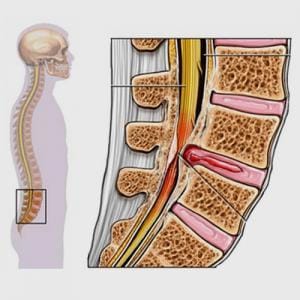

Throughout our lives, we have physical stress on our body, some acute such as falls, traumas, accidents and some chronic such as sitting for long periods, working at a desk for long periods, using computers or phones or standing for long periods. These physical stresses cause us to lose the normal alignment and put the spine in a weakened position. At first, this causes no pain but as it continues to abnormally load the spinal structures, it begins to break down the spinal structures leading to spinal damage and eventually the pain and functional loss to develop.